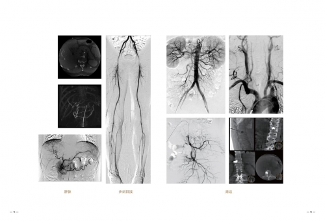

2019年,新一代的万东金刚DSA(减影血管造影设备)也成功出口多米尼加共和国。

在多米尼加国家血管医院,万东金刚DSA入驻仅仅三个多星期就帮助当地医疗专家成功完成了二十几台心脏手术。对于金刚DSA,当地专家认为:“操作便捷方便、图像细节丰富,令人折服。”

2019年,万东推DSA 家族的集大成者—— “金刚” DSA。金刚融入了国际先进的软件和硬件技术,产品运行更加稳定,图像更加清晰。

金刚DSA“八”轴运动结构,L臂、C臂、床台和谐动力配合,快速灵活实现术中各种摆位移动。智能全轴等中心,无论机架如何变化,图像视野中心始终保持不变,方便快速智能锁定病灶。

三段式移动床台方便使用 ,120CM大进深床面板,满足机架正位股动脉穿刺需求,230CM纵向移动范围,无需移动病人即可完成全身介入手术,80CM可移动地轨床,可迅速将C臂与床体分离,快速实现CPR位,方便抢救。

介入手术的剂量高低很关键,关系到医生和患者的安全。金刚DSA在每一环节减低剂量,采用40*30微剂量平板探测器,运用智能AI 算法和AICS低剂量统筹平台,兼顾精准与低剂量,使得医生和病人在手术过程中不用为辐射问题发愁。多种智能防碰撞技术,让设备在高速复合运动中,始终照顾周全。